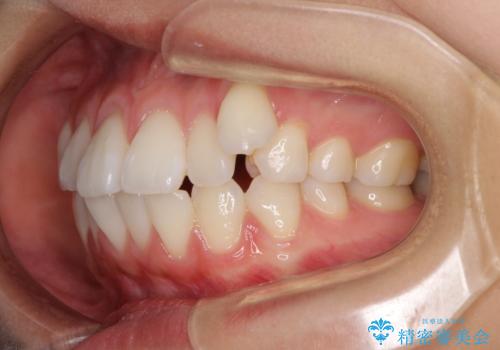

- 八重歯と口元の突出感を気にして来院された患者様です。

歯列が前方に突出しており、上下の正中がズレていたため、左側は上下第一小臼歯を、右側は上下第二小臼歯を抜去し、ワイヤー装置による矯正治療を行うこととしました。

当初はインビザラインによる矯正治療をご希望でしたが、正中を合わせたいことや、口元の突出感を改善したいことから、ワイヤー矯正を強く推奨しました。